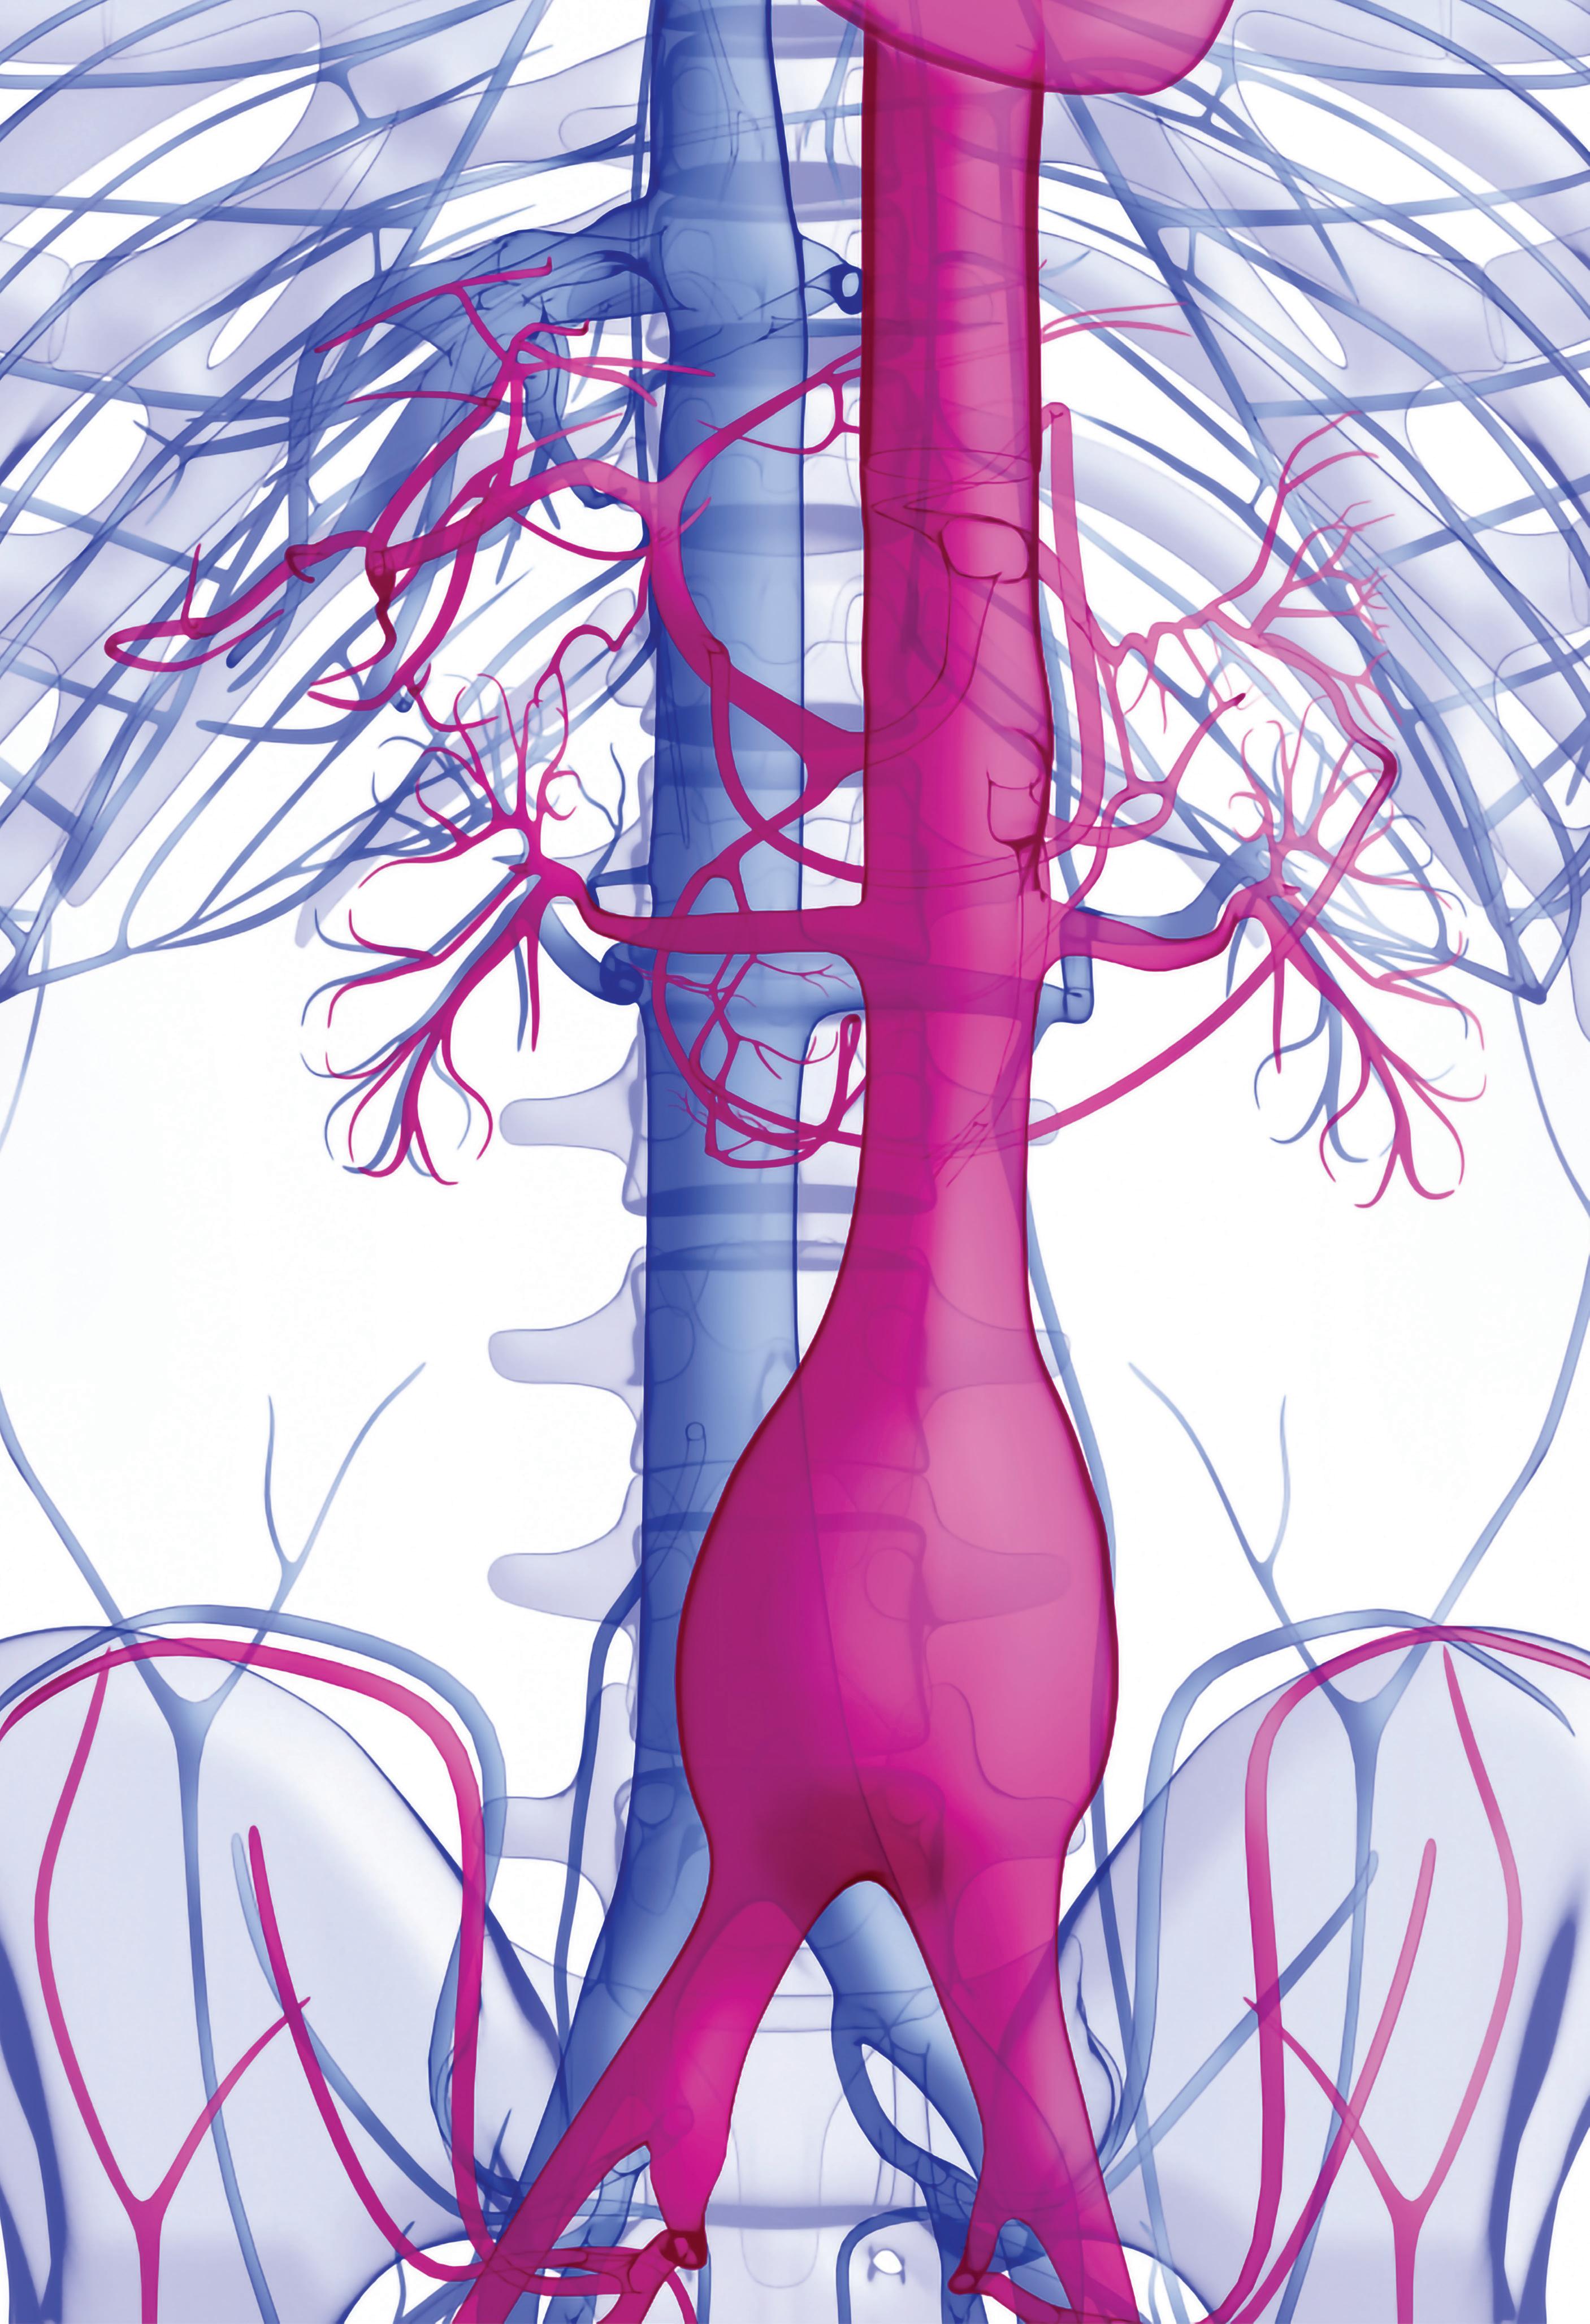

CX AORTIC VIENNA RETURNS THIS year for its third edition (24–26 October, Digital), bringing together world-leading specialists from the cardiac and vascular fields to discuss all facets of aortic care from selection to investigation, diagnosis, techniques and technologies. The meeting will showcase the latest approaches—open and endovascular—for the treatment of complex aortic problems spanning the aortic valve to the iliac arteries.

“This is, as always, a focus upon the aorta as managed by cardiac aortic surgeons, open vascular surgeons and endovascular surgeons; from the aortic

valve at one end, to the iliacs at the other end,” says Greenhalgh of the event’s 2022 edition. “CX Aortic Vienna, for those of you who have been to it before, is for all of those who manage the aorta,” he adds. “This is not just the surgeons, but the physicians—we have radiologists, imaging experts, vascular scientists and vascular nurses. All who manage aortic patients are welcome to come and join us for the digital edition on 24, 25 and 26 October this year.”

Multidisciplinary approach

The importance of multidisciplinary aortic approaches will be a key strand running through CX Aortic Vienna’s content and discussion, and the 2022 event will continue its mission to bring together specialists of all skills—be they cardiac, vascular or endovascular—to provide a comprehensive overview of cutting-edge aortic treatment.

The programme encompasses discussion and debate spanning key talking points in the aortic space including aortic arch interventions, thoracic dissection, thoracic imaging, thoracoabdominal techniques, juxtarenal, abdominal aortic and iliac artery therapies.